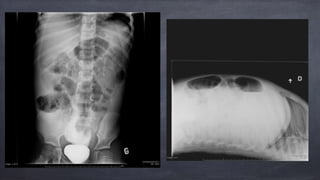

• 14.

Évaluation chez nous Urgence NPO Consult TRAUMA Écho abdo 5h15 Ascite important Doute sur perforation intestinale Aspect irrégulier de la vessie - perforation?

• 15.

Évaluation chez nous Urgence PSA Air libre ++++ Contraste (?!?) a/n 2 reins Contraste entre les anses digestives

• 17.

Passé à côté… Écho abdominale formelle effectuée au centre référant - 21h45 SCAN abdo-pelvien C+ fait au centre référant - 22h45 liquide libre perforation intestinale? pas de sonde urinraire en place, pas de contraste vessie